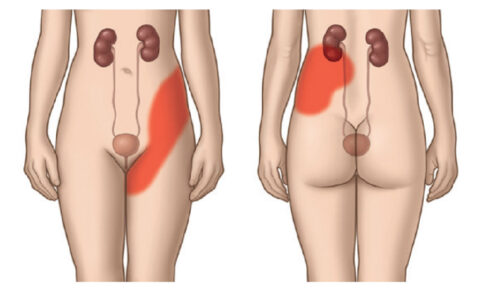

⚠️ Karaciğer Yağlanmasının Yaygın Belirtileri

- Sürekli yorgunluk

- Sağ üst karında dolgunluk hissi

- Şişkinlik

- Kilo vermekte zorlanma

- İnsülin direnci

- Ciltte matlık

⚠️ Çoğu kişide belirti vermeden ilerleyebilir; genellikle kan tahlili veya ultrason ile fark edilir.